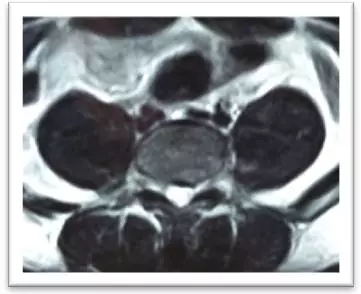

(術中)

4月8日,在局麻下,劉志安副院長親自實施了腰5/骶1椎間盤突出癥經(jīng)脊柱內(nèi)鏡髓核摘除術,術中摘除了大塊脫出髓核組織。